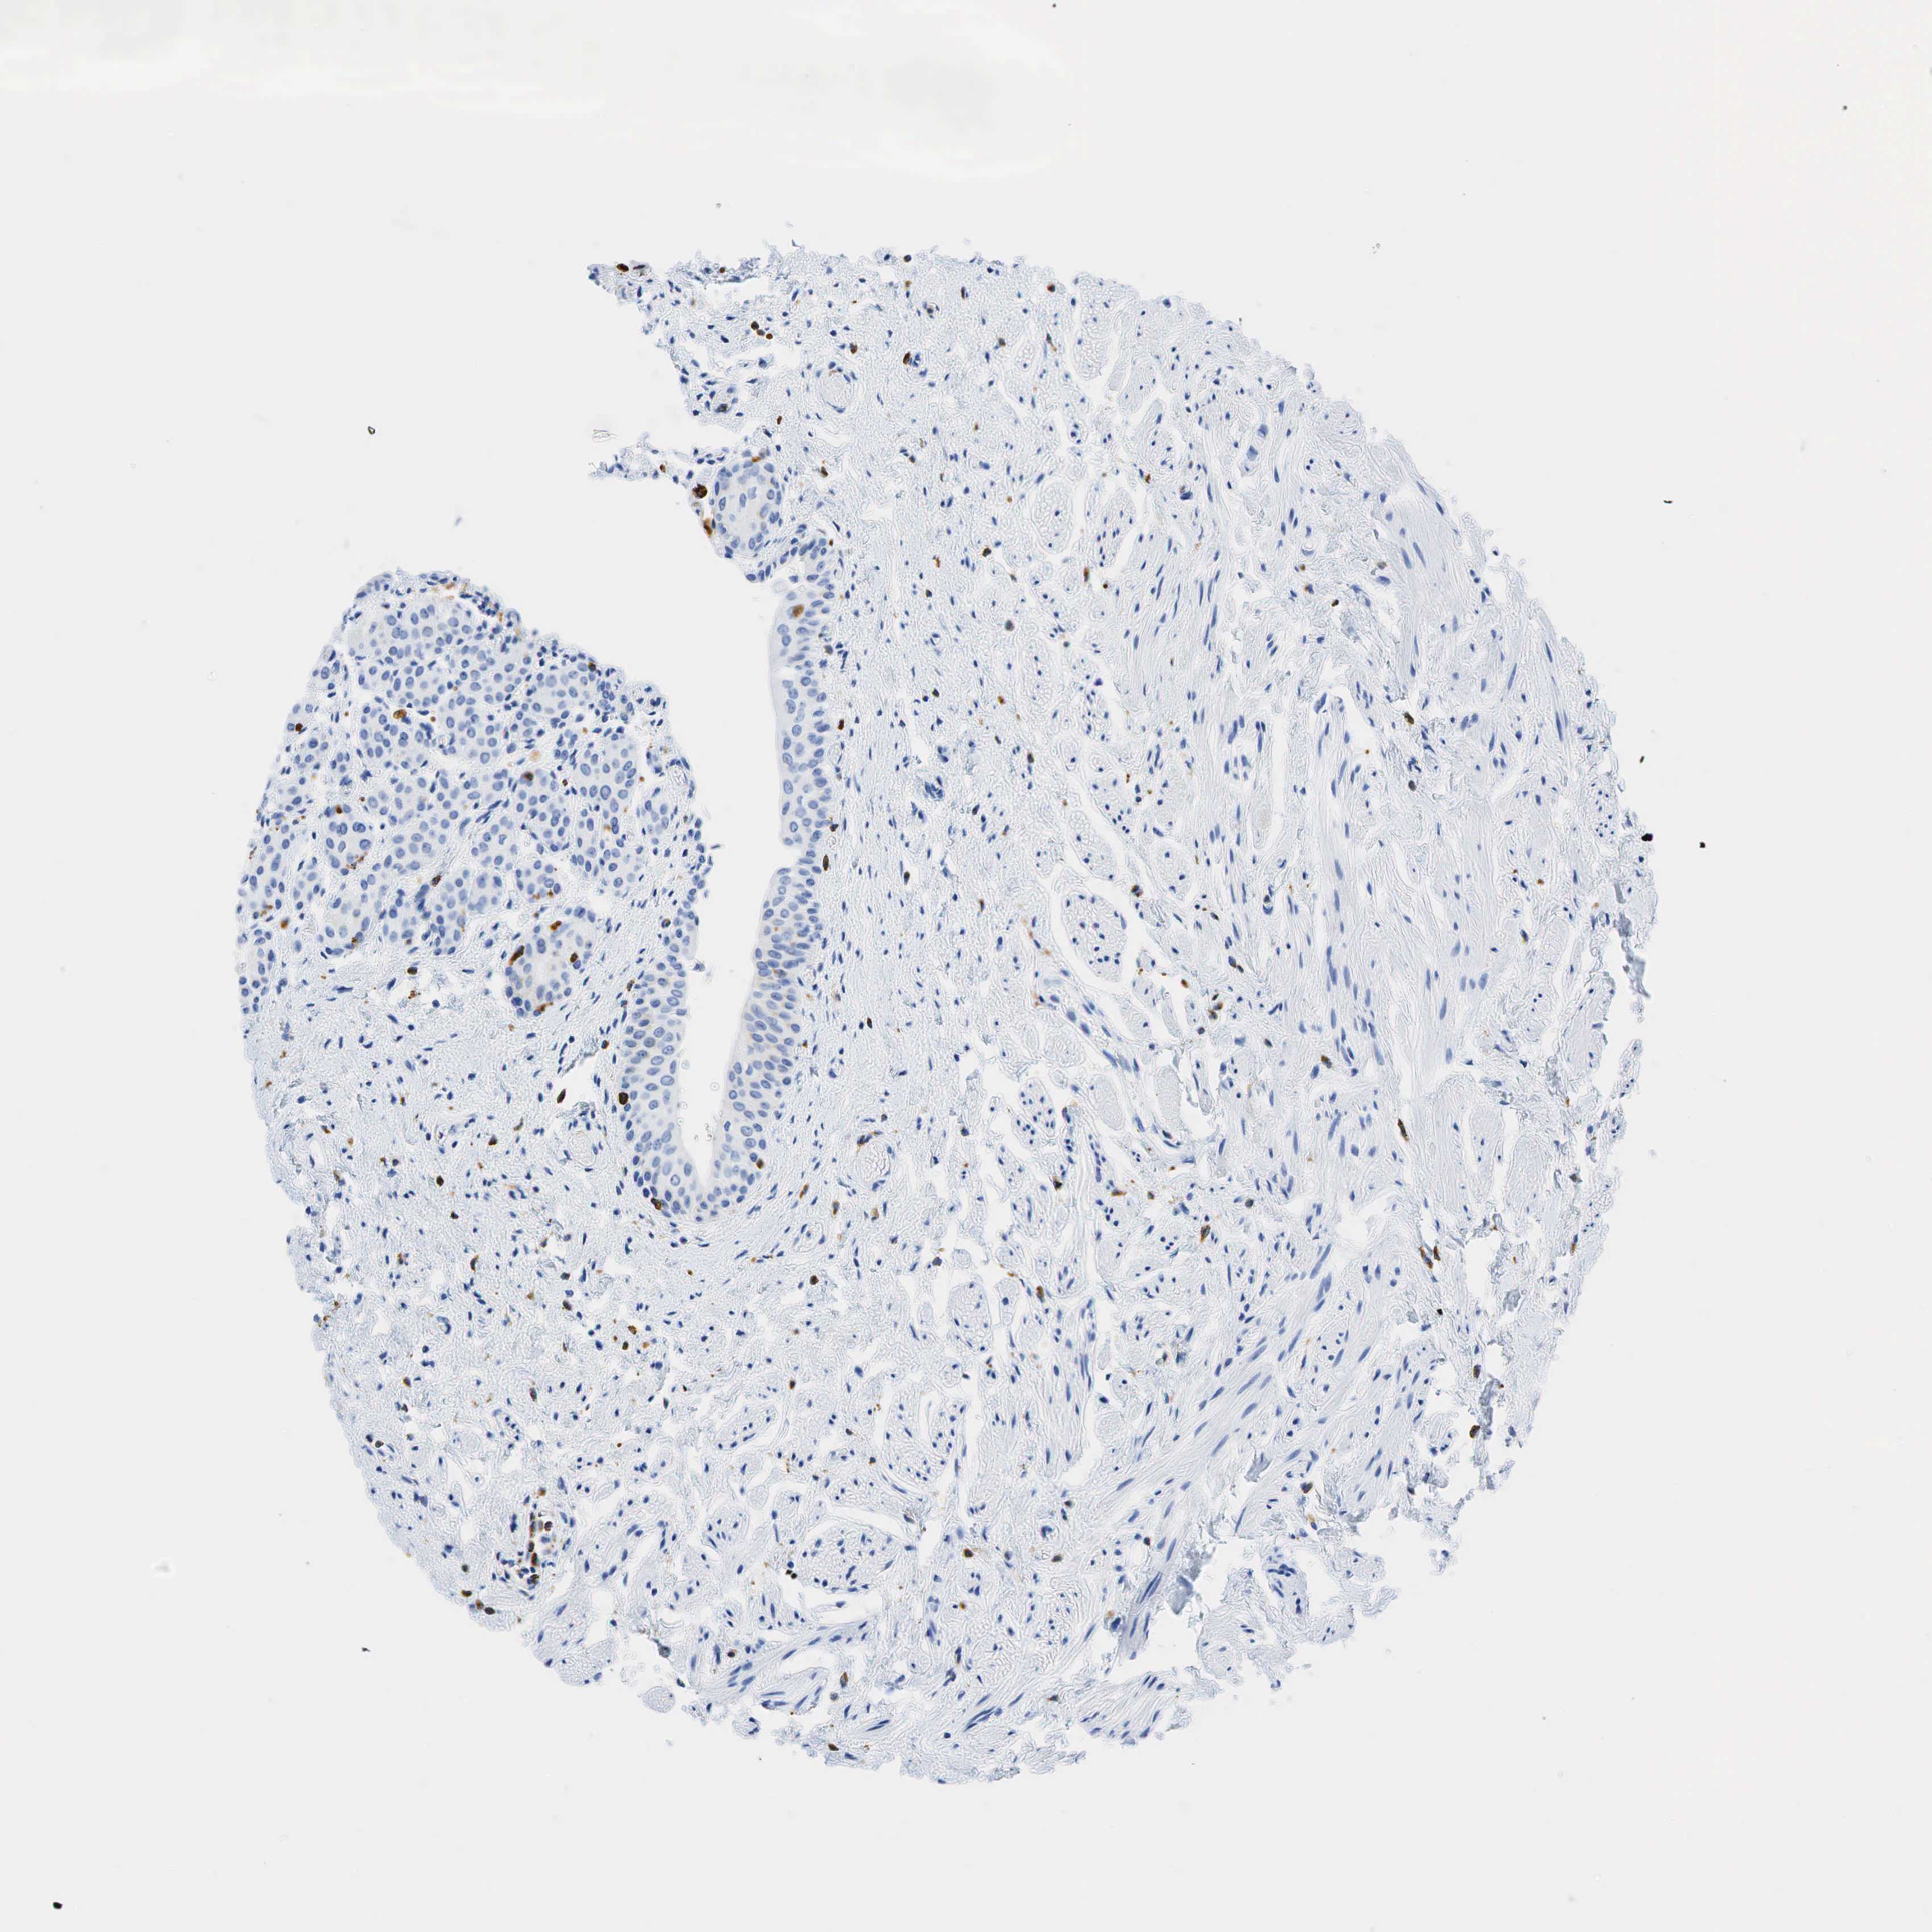

TISSUE PRIMARY DATA URINARY BLADDER Show tissue menu

URINARY BLADDER - Antibody stainingi

Antibody staining in the annotated cell types in the current human tissue is reported as not detected, low, medium, or high, based on conventional immunohistochemistry profiling in selected tissues. This score is based on the combination of the staining intensity and fraction of stained cells.

Each image is clickable and will lead to virtual microscopy that enables deeper exploration of all samples and also displays staining intensity scores, fraction scores and subcellular localization as well as patient and tissue information for each sample.

Antibody HPA048982Antibody CAB000051Antibody CAB000066Antibody CAB072861Antibody CAB072862

Urothelial cells Not detectedNot detectedNot detectedNot detectedNot detected